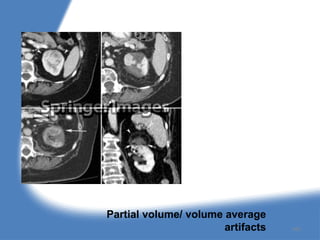

Artifacts in CT

5. Partial volume or volume averaging

Partial volume/ volume average

artifacts 160